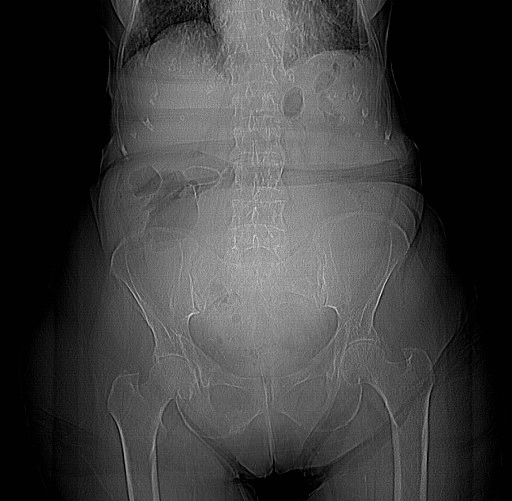

• Lách to (Splenomegaly)